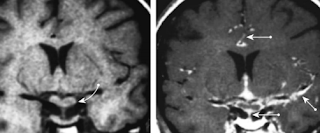

Case study: vertebral dissection

Young person, trauma, some C2 fractures. Concern for R vertebral artery dissection.

- Clots respond to flow. In a case of complete occlusion leading, the clot will propagate to the nearest point of flow-- in this case, the original occlusion/dissection was at C2-3, and the occlusion is complete. We would expect it to go all the way down to the origin. It hasn't -- there are 2 reasons. One is that there might not have been enough time. Two is that there are vessels causing flow somewhere along V1 or V2 keeping the vert patent. Big muscular branches or there's sometimes a big radiculomedullary branch (analogous to artery of adamkiewicz) that comes off around C5-6 -- this is very important; occlusion of this vessel may compromise high cervical spine vascular supply. One might think, in a case where the vert is still partially filling, if we fully occlude the vert there will be a lower stroke risk -- that might be the case, but if the vert is patent because there is flow to a large radiculomedullary branch, occluding it might lead to a devastating outcome.

- Complete occlusions typically do not have to be treated with anticoagulation as they are low embolic stroke risks. Partial or recannalized verts typically do have to be anticoagulated.